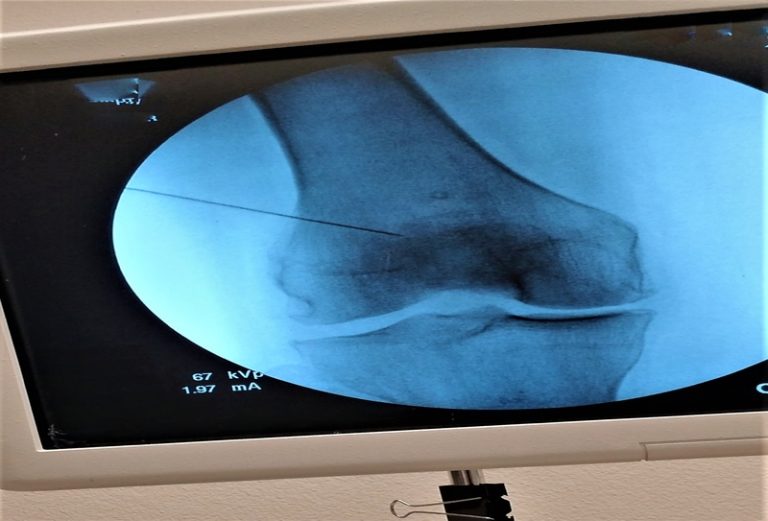

A patela é um osso sesamoide localizado na frente do joelho, encaixado no tendão do quadríceps. Ela desliza sobre o fêmur durante a flexão e extensão da perna, encaixando-se em um sulco específico chamado tróclea femoral. Sua estabilidade depende do alinhamento dos membros, da força muscular e de ligamentos que a mantêm na posição correta.

Por estar em uma área exposta, a patela também atua como uma espécie de escudo ósseo para a articulação anterior do joelho. Esse posicionamento a torna mais vulnerável a traumas diretos e condições relacionadas ao uso repetitivo, o que explica a alta incidência de dor patelar em pessoas fisicamente ativas.

Traumas diretos também podem levar a fraturas na patela do joelho, que variam de simples fissuras até fraturas deslocadas que exigem tratamento cirúrgico. O quadro clínico costuma envolver dor anterior no joelho, dificuldade de estender a perna e sensibilidade ao toque.